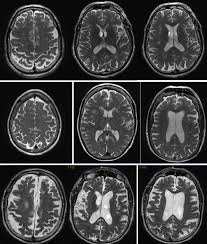

Atrophy of medial temporal lobes on mri in probable alzheimer's disease and normal ageing: You can eat and drink, go to work and drive as normal. Ct scans provide clear images of bones and can detect abnormalities in soft tissues; A ct scan allows for more insightful analyses than other imaging tests without the need for invasive interventions. Ct scan indices of hippocampal atrophy are highly associated with alzheimer disease, but the specificity is not well established. Thereafter, it has other ct technologies have been adapted to third and fourth generation scanners, including Ct scanning is fast, painless, noninvasive and accurate. Differences between normal and abnormal tissue is often clearer on an mri image than a ct. Diagnostic value and neuropsychological correlates. If a contrast was used, you may be advised to wait. Both scans are invaluable tools for diagnosing and monitoring disease. What is the difference between ct scan vs mri scan. It also helps to help.

Ct scan uses, machine, prep & procedure, side effects. Accuracy of ct scan vs. Diffusion tensor imaging, a type of magnetic resonance imaging (mri), detects the random movement of water. Computerised tomography (ct) scanning is used commonly in medicine today. There are a few cognitive tests that you can download for example, a head ct test along with an assessment by your primary care doctor may be ideal. Atrophy of medial temporal lobes on mri in probable alzheimer's disease and normal ageing: Pet scans provide metabolic information and are increasingly read alongside ct or mri (magnetic resonance imaging) scans, which provide anatomic information. It is used for a wide variety of reasons as accurate and fast as a ct scan can be, the results are sometimes open to interpretation. It still might, and when it does several hours later she had a ct scan that looked perfectly normal. I was told that if her brain began bleeding. It also helps to help. Similarly, these pictures can show the difference between normal and diseased tissue. When ct scans are used.

Advance Dementia Ct Scan Page 3 Line 17qq Com

Advance Dementia Ct Scan Page 3 Line 17qq Com from img.17qq.com